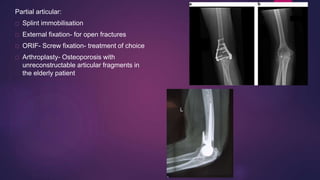

Partial articular:

Splint immobilisation

External fixation- for open fractures

ORIF- Screw fixation- treatment of choice

Arthroplasty- Osteoporosis with

unreconstructable articular fragments in

the elderly patient

Complete articular:

External fixation

ORIF- plate fixation- Treatment of

choice

Arthroplasty- Osteoporosis or

very low transverse fracture

pattern with unreconstructable

articular fragments in the elderly

patient